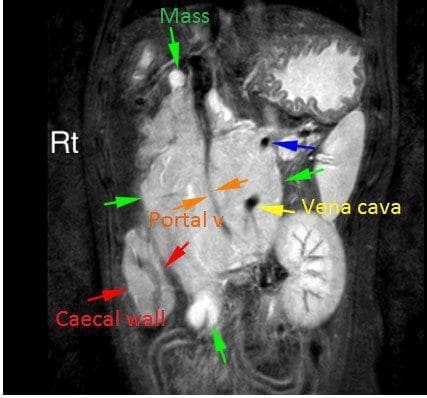

The MRI confirmed a multilobular irregular shaped mass in the cranial abdomen, which measures16cm (craniocaudal) x 6.9 cm (dorsoventral) x 8.0 cm (transverse). The mass surrounds the portal vein and branches of the portal system, the cranial mesenteric artery, and is resulting in a severe regional mass effect. The mass has a broad region of contact with the celiac artery, the distal ileum (at the level of the ileocolic junction), the caudal vena cava, and the ascending and transverse colon. At the level of contact with the colon, there is marked circumferential wall thickening, measuring up to 8 mm thick. There is also moderate diffuse thickening of the caecum. The margins of the pancreatic body and left pancreatic limb are in contact with this mass. Within the mid- to caudal aspect of the mass, there is marked narrowing of the portal vein and caudal vena cava. The jejunal lymph nodes are not seen. Multiple tortuous vessels are present along the periphery of the mass, most notable along the caudoventral margin. The pancreaticoduodenal vein is markedly tortuous, and subjectively enlarged, with a normal termination of the gastroduodenal vein into the portal vein. The right and left kidneys are moderately asymmetric, measuring 5.6 cm and 7.8 cm, respectively. The right kidney maintains a normal shape and similar signal intensity to the left. The adrenal glands are seen and unremarkable.

Diagnosis: Inoperable mesenteric mass involving major vessels and intestine

Large, extensive, mesenteric mass, with involvement of the ileocolic junction, transverse

colon, and perivascular involvement of the portal vein, caudal vena cava, and cranial

mesenteric artery. Organs of origin include colon/ileum, mesenteric, or lymph node (pancreas is possible).

There is evidence of collateral portal-portal venous shunting. The colonic and caecal wall thickening may be secondary to lesion extension, or regional oedema, inflammation, or haemorrhage. The T2 and STIR hyperintensity within the mass may represent necrosis, haemorrhage, or lymph.